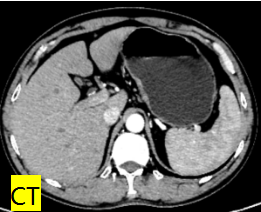

64岁王某,4月前在兰州某医院确诊为胃癌(cT2NxM0),因合并肺气肿、高血压3级、乙肝及脑出血病史,且长期口服抗凝药物,存在手术相对禁忌症,遂给予2周期SOX方案新辅助化疗,期间积极处理合并症。2周期化疗后行胃镜检查提示:贲门病变性质待查(化疗后改变)。病检提示:(贲门)高分化腺癌。CT检查提示:贲门小弯侧胃壁局部略增厚,浆膜面光整。该患者经术前新辅助治疗后病情进一步缓解,且病灶局限,无淋巴结及远处转移,治疗以手术首选,但考虑到患者年龄较大,合并症较多,在保证肿瘤R0切除的前提下为降低围手术期并发症,经与家属充分沟通各类术式的近远期疗效及并发症后最终决定行近端胃切除术。然而考虑到目前近端胃切除后不论是间质空肠、双通道吻合还是胃食管直接吻合,术后反流性食管炎等相关并发症发生率均较高,而Kamikawa吻合可减少反流性食管炎的发生率,并降低了吻合口瘘的风险,但是操作相对复杂,手术时间长,考虑到该患者基础疾病较多,可能不能耐受较长的手术时间。研究报道GIRAFFE重建操作相对简单,手术时间短且有很好的抗返流效果,消化病院区胃外科腹腔镜胃癌团队在聂蓬主任的带领下紧跟胃癌诊疗国际前沿,深入学习探讨,积极临床实践,在做好充分的术前准备的基础上,成功为该患者开展了腹腔镜下近端胃切除后食管胃GIRAFFE重建,手术效果良好。